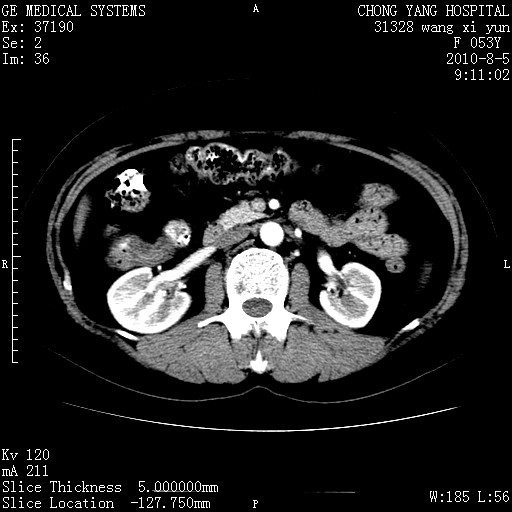

标题: CT28214:F41Y 血尿二十天,建议盆腔平扫加增强。

胆管细胞ca?

1)考虑肝左叶胆管细胞癌。2)脂肪肝。

支持胆管细胞ca。